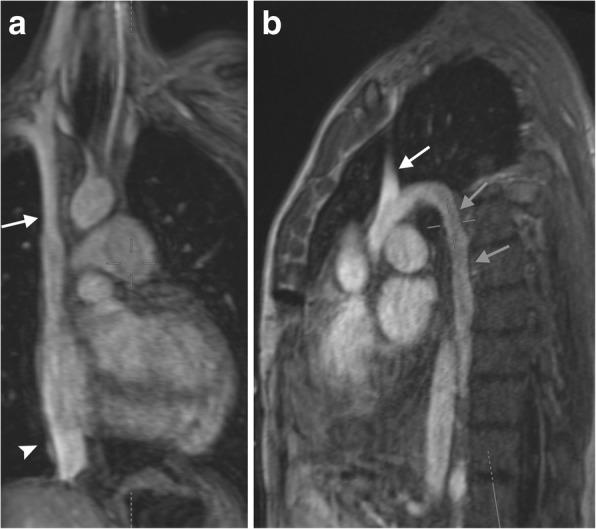

In the healthy patient, blood returns to the heart via classic venous pathways. Obstruction of any one of these pathways will result in blood flow finding new collateral pathways to return to the heart. Although significant anatomic variation exists and multiple collateral vessels are often present in the same patient, it is a general rule that the collateral pathways formed are a function of the site of venous blockage. Therefore, knowledge of typical collateral vessel systems can provide insight in localizing venous obstruction and characterizing its severity and chronicity. In addition, knowledge of collateral anatomy can be essential in interventional procedural and/or surgical planning, especially when placing catheters in patients with venous blockage. In this pictorial review, we provide a systematic approach to understanding collateral pathways in patients with venous obstruction in the upper body.

在健康患者中,血液通过经典静脉途径回流至心脏。这些途径中任何一条受阻都会导致血流寻找新的侧支途径回流至心脏。尽管存在显著的解剖变异,且同一患者体内常存在多条侧支血管,但一般规律是,形成的侧支途径取决于静脉阻塞的部位。因此,了解典型的侧支血管系统有助于定位静脉阻塞并判断其严重程度和慢性化情况。此外,了解侧支解剖结构对于介入操作和/或手术规划至关重要,尤其是在为静脉阻塞患者放置导管时。在本图文综述中,我们提供了一种系统方法,用于理解上身静脉阻塞患者的侧支途径。